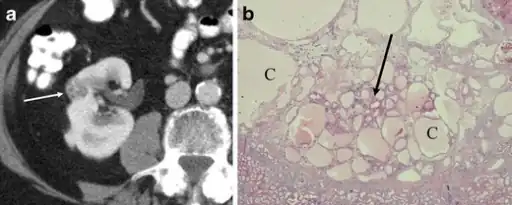

a,b)Renal oncocytoma with cystic change.

In gross appearance, the tumors are tan or mahogany brown, well circumscribed and contain a central scar. They may achieve a large size (up to 12 cm in diameter).

The main differential diagnosis of renal oncocytoma is chromophobe renal cell carcinoma oncocytic variant, which like the renal oncocytoma has eosinophilic cytoplasm, but has perinuclear clearing and, typically, some degree of nuclear atypia.